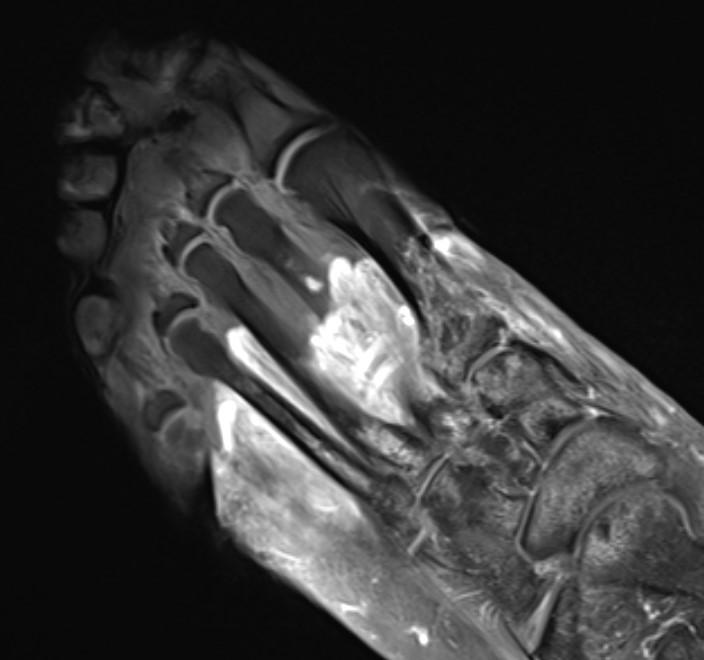

MRI of the foot in a patient with severe COVID-19. The grey part of the foot is devitalized tissue (gangrene).

Northwestern University